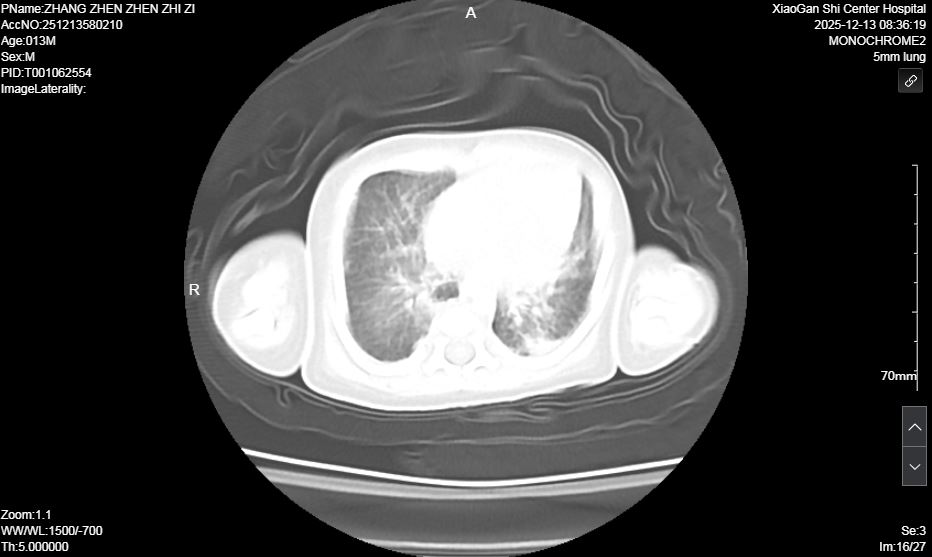

术前肺部超声及CT均提示双肺实变明显

面对挑战,新生儿科迅速启动多学科会诊(MDT),联合呼吸内科、儿童呼吸科、中心试验室等科室专家深入讨论。在充分与家长沟通并取得同意后,医疗团队成功为患儿实施了本市首例新生儿纤维支气管镜和肺泡灌洗术,同时取灌洗液进行 NGS检查、明确病原学诊断,团队快速调整个性化诊疗方案,精准调控参数、严密监测病情,稳步推进阶梯式撤机脱氧,全力攻克救治难关。